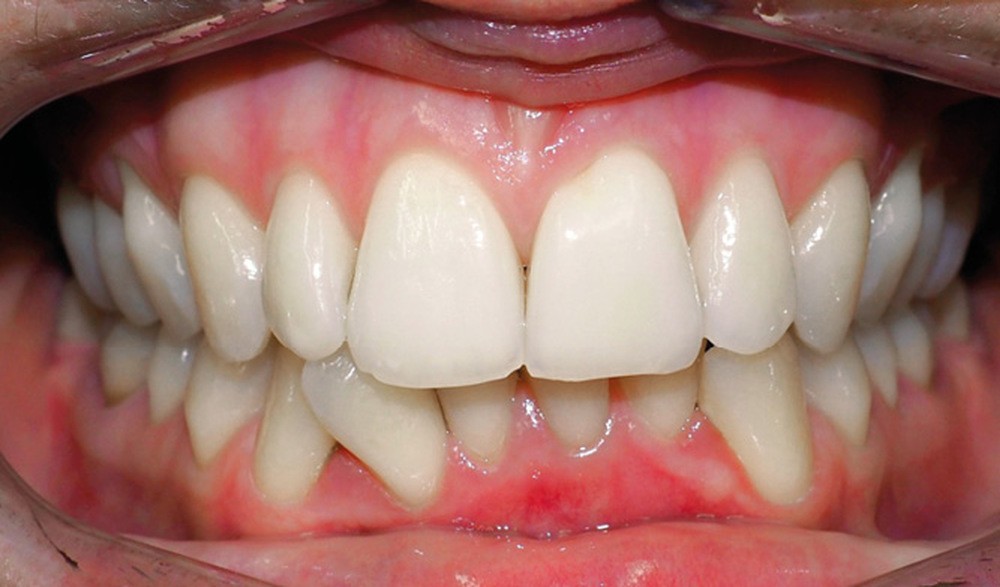

Discussion (fig. 4 à 7)

La durée du traitement a été de vingt-trois mois. Des mouvements lents ont permis un contrôle des axes incisifs mandibulaires.

Le stripping maxillaire a permis :

- de rééquilibrer les dimensions entre les incisives centrales et latérales (DDD initiale par insuffisance maxillaire) ;

- d’éviter l’apparition de triangles noirs entre les incisives [3] ;

- d’éviter la présence d’un surplomb résiduel.

Des triangles noirs sont apparus à la mandibule suite à l’extraction de 31 : ils ne sont pas exposés lors du sourire, ce qui n’entraîne pas de défaut esthétique.

La génioplastie discrète apporte un équilibre facial et une fermeture labiale non forcée, ce qui limite le risque de récidive liée à la pression musculaire.

La superposition des structures anatomiques nous montre une ingression de l’incisive mandibulaire et un maintien de l’axe ainsi qu’une distalisation en gression de l’incisive maxillaire.